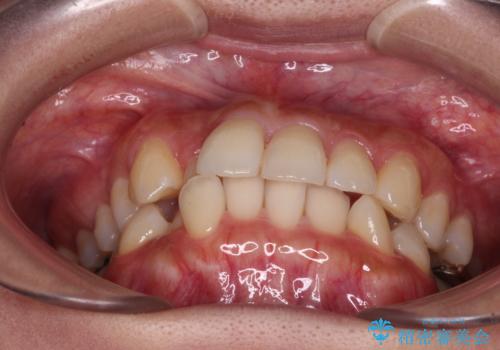

- 前歯のクロスバイトと口元の膨らんだ横顔の印象を気にして来院された患者様です。

ご本人の気にされている口元は、分析数値からするとそれほど突出しているものではありませんでした。

しかしながら。そのまま叢生を解消すると横顔が突出した印象になる可能性が高かったため、上下左右の小臼歯4本を抜歯して、ワイヤー装置にて矯正治療を行うこととしました。